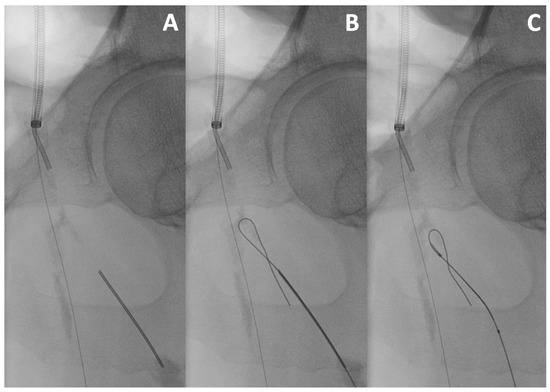

Kissing Stenting Technique

Stenting with Fenestration of the Healthy Ostium

T and Small Protrusion (TAP) Technique

Culotte Technique